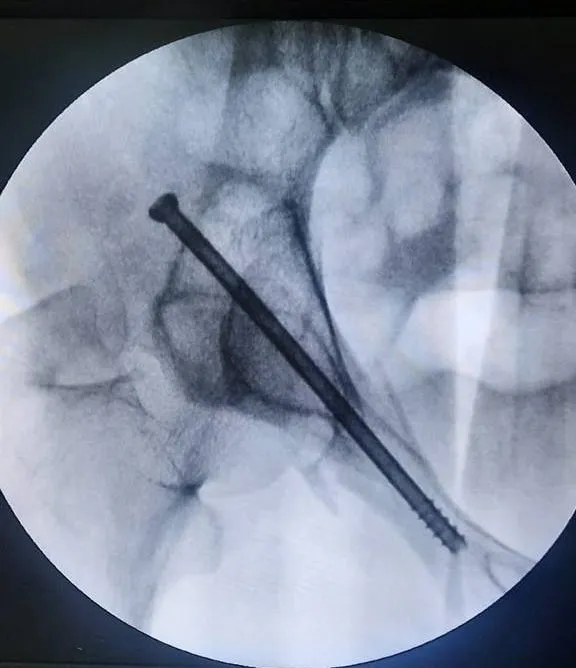

В приемное отделение Волоколамской больницы привезли 36-летнего мужчину в критическом состоянии. Он получил на стройке серьезные травмы из-за упавшей на него стены из кирпича.

После осмотра пациента медики нашли множественные переломы костей таза, лодыжки и ушиб брюшной стенки.

Травматологическая бригада впервые выполнила столь сложную операцию. Они использовали металлоконструкции для правильного восстановления костей таза. Все прошло успешно, сейчас мужчина чувствует себя намного лучше и занимается восстановлением под контролем специалистов.

«Этот маленький шаг является началом большого пути к развитию тазовой хирургии в нашей больнице. В настоящее время оснащенность больницы, опыт и квалификация специалистов позволяют выполнять подобные оперативные вмешательства на постоянной основе», — рассказала главный врач Волоколамской больницы Анжела Магомедова.